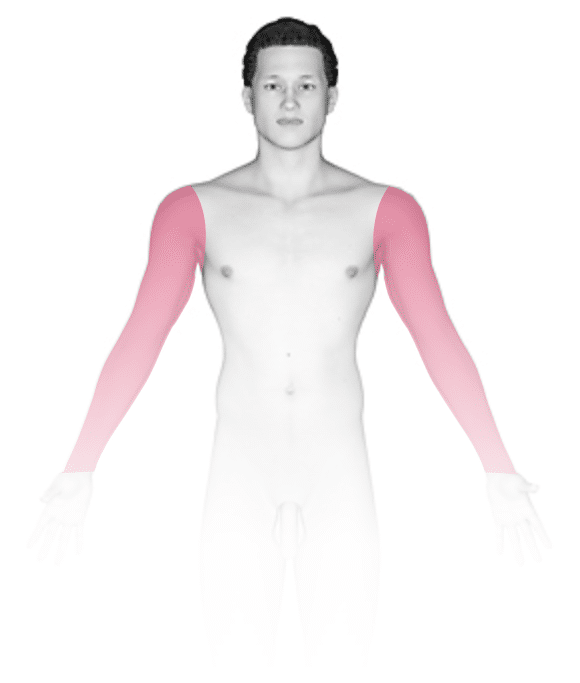

Bulging, cord-like, twisted, soft, blue-to-purple swellings are seen on the legs, anywhere from the groin to the ankle. Many times there are no symptoms, but some people complain of burning, throbbing, muscle cramping, swelling, or an achy or heavy feeling in the legs.